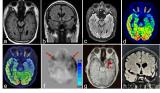

世界首个!移动光子计数CT获批

近日,三星电子有限公司的子公司 NeuroLogica Corp. 今天宣布,其先进的OmniTom Elite已获得 510(k) 许可,以增加光子计数检测器 (PCD) 技术。 2022-03-14 X射线装置CT扫描